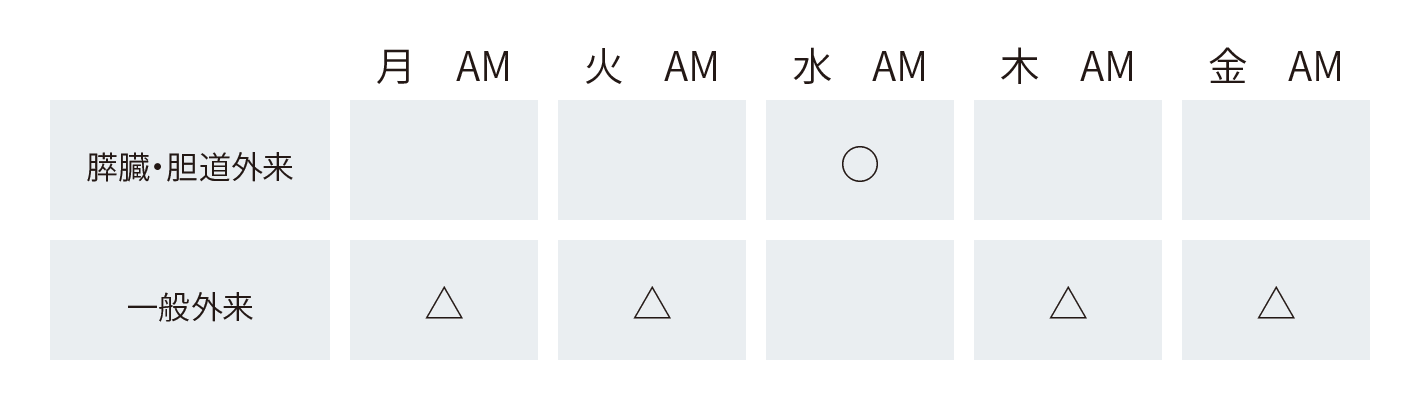

膵臓・胆道に不安のある方で直接、センターへの受診を希望される場合は水曜日の午前以外でも外科一般外来で診察をおこなっております。